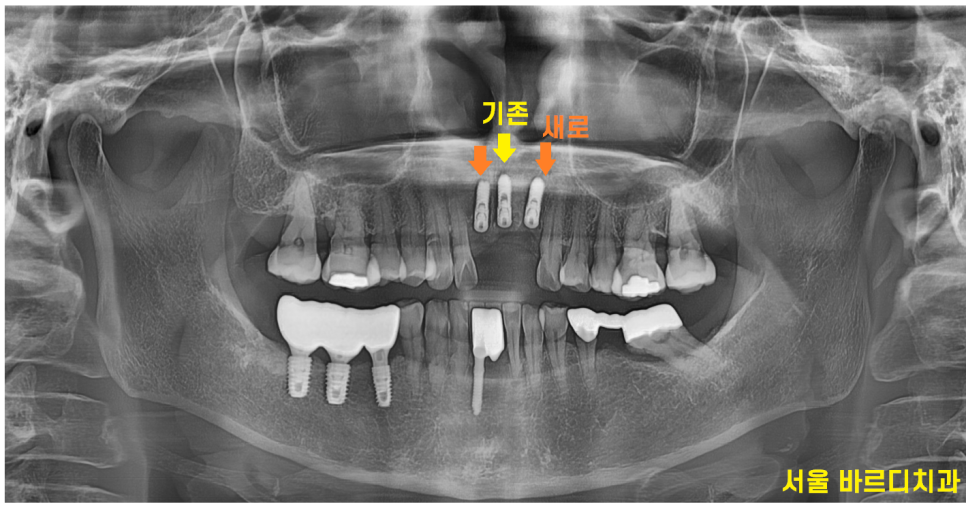

앞니에 임플란트 한 것도 보이고

보철로 씌운것도 있더라고요~

ct 사진을 분석해보니

빨간색 동그라미 부분을 봐주세요.

까만 부분이 보이시죠?

이 부분이 뼈가 녹은 부위인데

한쪽 벽면이 다 녹았습니다.

윗니 앞니 흔들림 증상 외에도

뼈가 치아를 붙잡아주지 못해

치아가 자꾸 내려오고

뻐드러져 보이는 현상 발생

문제 해결을 위해서는 최소 2개 치아는 뽑아야

불편감을 해소해드릴 수 있었습니다.

231107

뽑고 임플란트를 해야하는 치아 사이로

이미 예전에 해둔 임플란트 치아가 있었습니다.

가운데 낀 형태죠.